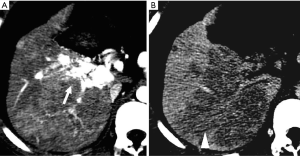

Changes of parenchymal enhancement in the liver and spleen

Reversed portal flow shunting of arterial contrast caused by HAPS leads to decreased splenic enhancement and increased hepatic enhancement on HAP images (Figure 4). Therefore, (I) the enhancement of the liver is significant, while that of the spleen is decreased during the HAP; and (II) the density (signal intensity) of the liver is close to or even higher than that of the spleen.